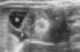

Peritoneal fluid

Peritoneal fluid is a serous fluid made by the peritoneum in the abdominal cavity which lubricates the surface of tissue that lines the abdominal wall and pelvic cavity. It covers most of the organs in the abdomen. [Source: Wikipedia ]